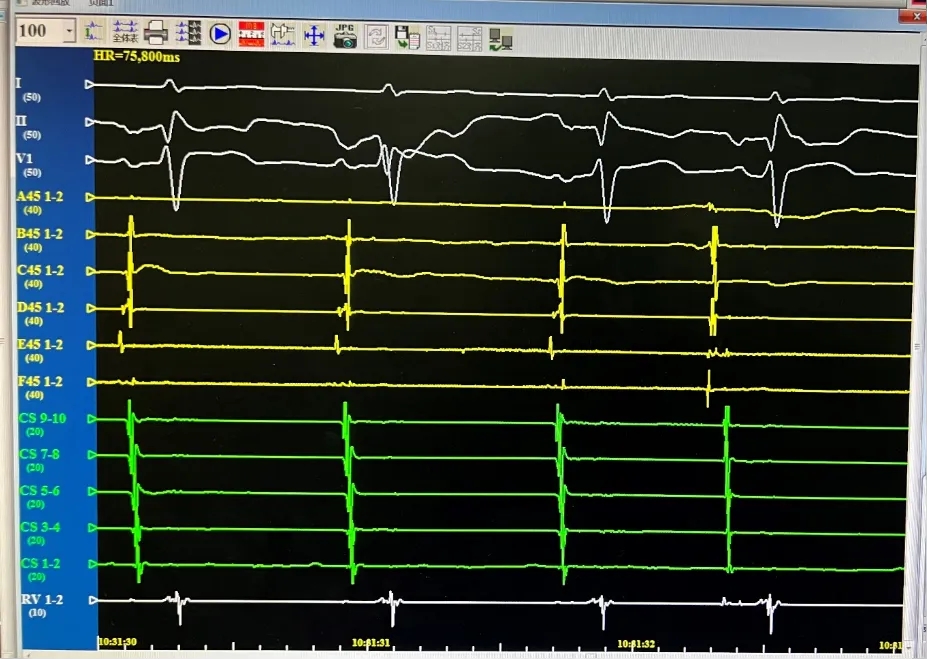

术中均直接采用CardiPulse®脉冲电场消融自身标测电极进行了电位标测,消融即刻及消融结束后四根肺静脉电位消失并双向传导阻滞,结果满意。

LSPV,消融前后电位。消融后电位即刻消失。

LIPV,消融前后电位。消融后电位即刻消失。

RSPV,消融前后电位。消融后电位即刻消失。

RIPV,消融前后电位。消融后电位即刻消失。

消融完成后,分别进行四支肺静脉电位验证。电位无恢复,证明传入阻滞。起搏电极,无法带起心房证明传出阻滞。